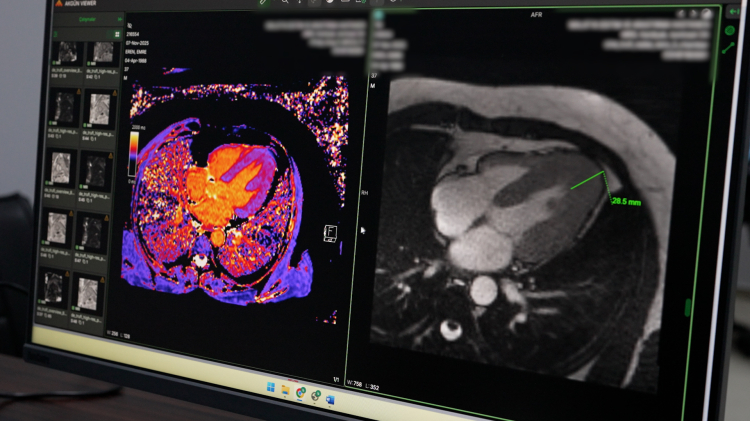

Hastanede yeni başlatılan önemli uygulamalardan birinin de kardiyak MR olduğunu ifade eden Doç. Dr. Bülent Petik, bu yöntemin günümüzde kalp kası hastalıkları, kapak hastalıkları ve damarsal anomalilerin değerlendirilmesinde dünyada ön sıralarda yer aldığını söyledi. Kardiyak MR sayesinde kalp kası yapısının detaylı olarak incelenebildiğini belirten Petik, birçok hastalığın tanı ve tedavi planlamasının artık bu görüntüleme yöntemi üzerinden yapıldığını ifade etti.

Açıklamalarında örnek bir vakaya da değinen Doç. Dr. Bülent Petik, 35-40 yaşlarında erkek bir hastanın kalp yetmezliği şikâyetiyle kendilerine yönlendirildiğini belirtti. Yapılan kardiyak MR incelemesinde hastanın sol ventrikül duvar kalınlığının yaklaşık 30 milimetreye ulaştığının tespit edildiğini ifade eden Petik, bu durumun hastanın yaşam kalitesi ve performansını ciddi şekilde etkilediğini söyledi.

Söz konusu hastalığın klasik anjiyografi ile anlaşılmasının mümkün olmadığını belirten Petik, ancak ileri kardiyak görüntüleme yöntemleriyle tanı konulabildiğini vurguladı. Hastaya Yamaguchi Sendromu olarak bilinen özel bir kalp kası hastalığı tanısı konulduğunu söyleyen Petik, erken tanı sayesinde uygun tedavi planlamasının yapıldığını ve ilerleyen dönemde oluşabilecek ciddi kalp yetmezliği riskine karşı önlem alınabildiğini ifade etti.